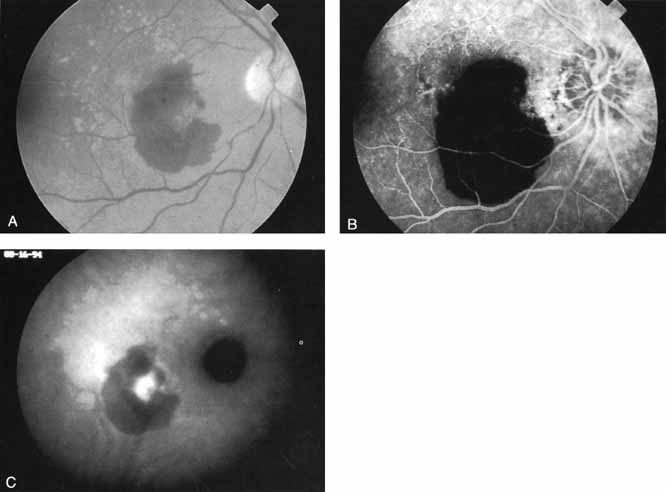

Most promising in this category of inflammatory choroidopathies is a better detection and understanding of the lesions of multifocal choroiditis. Multiple large, scattered, hypofluorescent spots are seen on ICG angiography, particularly in the later phases of the angiogram69 (Fig. 18). These lesions are not evident either on clinical examination or on fluorescein angiography. In addition to having these larger hypofluorescent lesions, patients with multifocal choroiditis have smaller dot-like lesions and hyperfluorescent foci that do not correlate with lesions seen clinically or by FA. They involve the posterior pole and in some patients extend into the mid-periphery. There is also a “papillotropic” involvement, with confluent hypofluorescent lesions surrounding the optic nerve,69 which may be useful in understanding the associated blind-spot enlargement evident in this condition.70 Other zonal visual field defects have been associated with this condition,70 and corresponding ICG abnormalities have been documented in some patients.69

Fig. 18 A. Clinical photograph of a patient with active inflammation associated with multifocal choroiditis. An atrophic scar from previous laser photocoagulation treatment is noted in the temporal macula. The patient reported visual disturbance, and an enlarged blind spot was noted on visual field testing. B. Late-phase indocyanine green study demonstrating a multitude of hypofluorescent spots that were larger than those seen with multiple evanescent white dot syndrome and more numerous and more extensively distributed than appreciated on clinical examination. Note that there is marked confluence of these lesions around the optic nerve, which may help to explain the enlarged blind spot noted on visual field testing.

Natural history data indicate that with progressive increase in vitritis and associated choroidal inflammation, an increase in the number and extent of these hypofluorescent lesions can be documented.40 Furthermore, use of oral steroid therapy as a means of controlling this inflammatory process has been documented to produce not only clinical resolution of the inflammatory process but also corresponding resolution of the hypofluorescent lesions seen on ICG angiography.69 These clearly demonstrated lesions not only may lead to a better understanding of the process of inflammation involved in multifocal choroiditis and potential management strategies but also may serve to differentiate this condition from the ocular histoplasmosis syndrome.